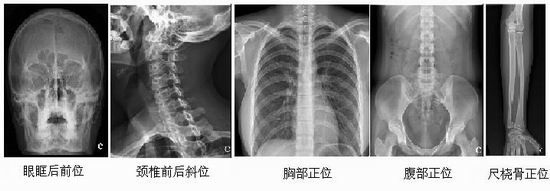

名称:直接数字化X线成像系统(Digital Diagnost VR)

主要功能:飞利浦的Digital Diagnost VR采用了最先进的探测器技术,具有ISO800的感光灵敏度,极佳的光量子转换效率,可以以较低的剂量获得高质量的图像,既能减少X线对操作者和患者的损伤,又延长了球管的使用寿命。采用DDR动态范围扩展图像处理软件,最大限度地增加了影像的动态密度范围,严格保持信息的正确性,不会产生伪影,为医生获得丰富的诊断信息。系统极高的自动化操作系统,快速显示图像信息,无需等待,极大地提高了工作效率和病人检查速度。